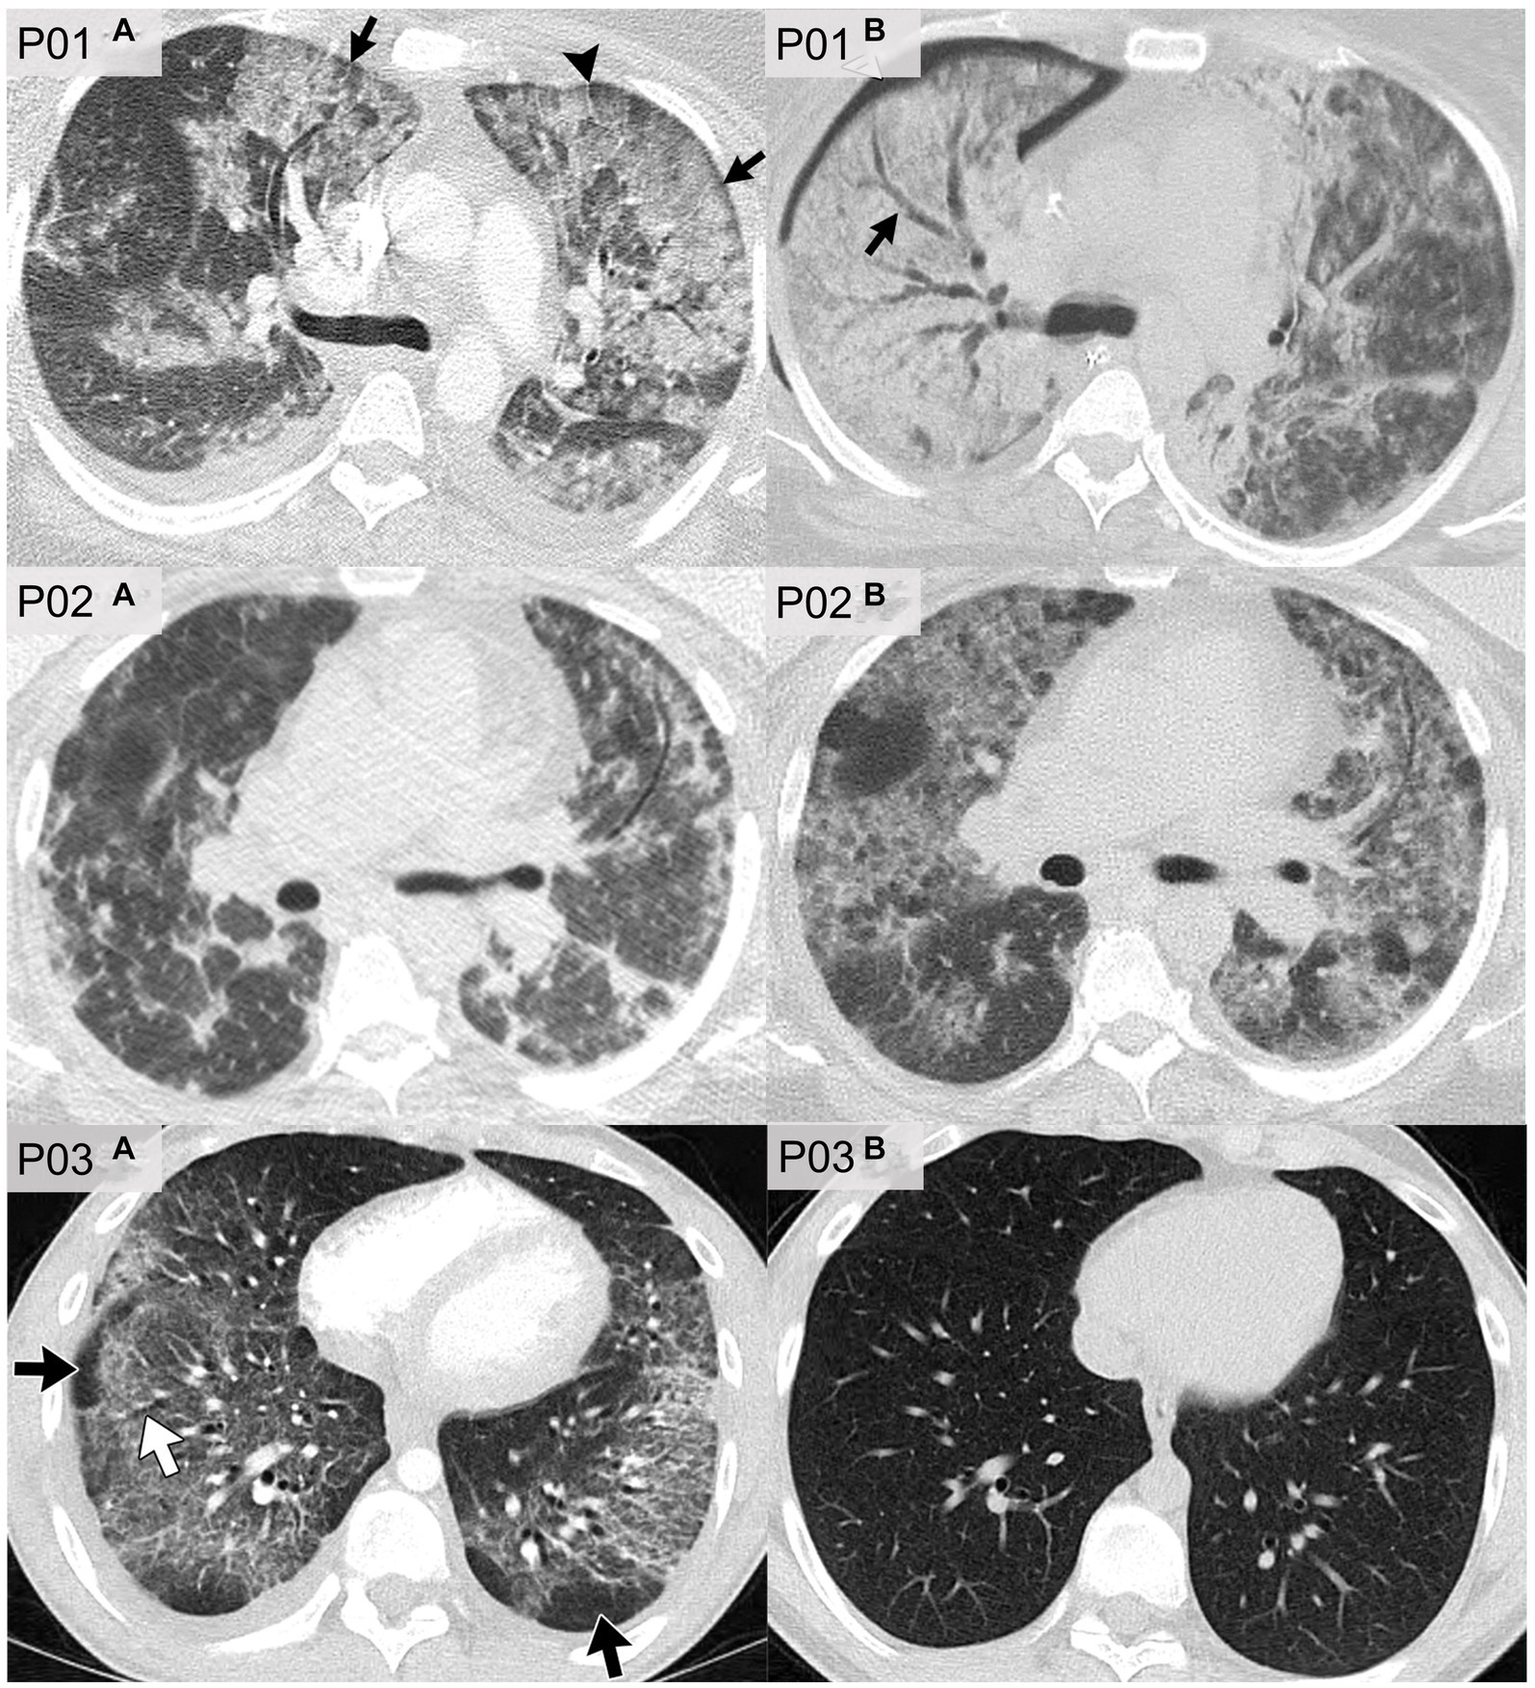

Figure 6 shows axial CT slices of three patients, each at two separate time-points, previously published and described by Kligerman et al. (94). P01 was a 35 years-old female who reported the use of THC-based e-cigarettes and who presented with CT evidence of ground-glass opacities and consolidations as well as subpleural and perilobular sparing (P01a). CT images that were acquired 2 weeks later (P01b) showed extensive consolidation along with areas of bronchial dilation and the development of a right pneumothorax; this patient died 5 days later. P02 was a 51 years-old female who reported the use of nicotine-based e-cigarettes and who presented with CT evidence of ground-glass opacities and subpleural sparing (P02a). Two months later (P02b), CT images revealed more extensive ground-glass opacities and septal thickening which presented as “crazy paving” pattern. P03 was a 20 years-old male who reported the use of both THC- and nicotine-based e-cigarettes. CT imaging (P03a) in this patient revealed organizing pneumonia, peribronchiolar ground-glass opacities and subpleural sparing. CT imaging 4 weeks later (P03b) normalized, after the patient was treated with steroid therapy.

Figure 6

CT imaging of e-cigarette-related or vaping-associated lung injury (EVALI) with short-term follow-up. P01: axial CT of a 35 years-old female with diffuse alveolar damage pattern who vaped THC. (A) CT imaging showed ground-glass opacities with areas of consolidation, subpleural and perilobular sparing (arrows) and septal thickening (arrowhead). (B) CT 2 weeks later showed extensive right lung consolidation with areas of bronchial dilation (arrow) and internal development of right pneumothorax. Patient died 5 days later. P02: axial CT of a 51 years-old female showing multiple episodes of EVALI following repeated vaping of nicotine with mint flavoring. (A) CT imaging showed scattered areas of ground-glass opacities with subpleural sparing. (B) Two months later, the patient returned to emergency department with dyspnea and fever. CT findings included more extensive ground-glass opacities with areas of lobular and subpleural sparing. Septal thickening is present creating “crazy paving” pattern. Patient’s condition deteriorated, and was complicated by aspiration pneumonia and bilateral lower-lobe collapse. P03: axial CT of organizing pneumonia pattern in a 20 years-old male who vapes nicotine and THC products daily. (A) CT imaging showed peribronchiolar ground-glass opacities with subpleural sparing (black arrows). Areas of bronchial dilation are seen in areas of ground-glass opacities (white arrow). (B) Four weeks following steroid therapy, the patient’s CT scan was normal. Images reproduced with permission from Kligerman et al. (40).